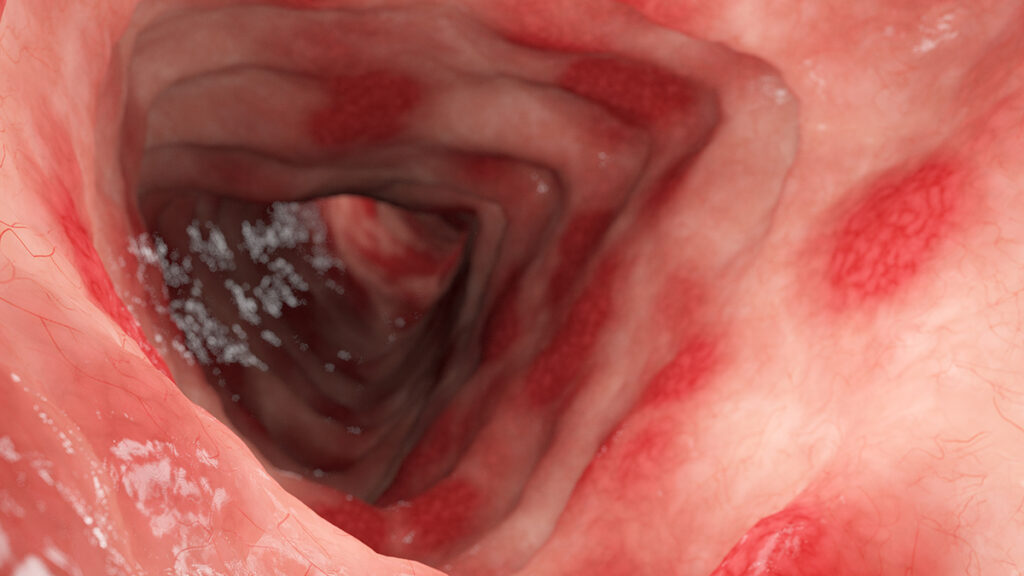

⑴消化器疾患と栄養の相互作用胃や腸の疾患、特に消化性潰瘍(胃潰瘍・十二指腸潰瘍)、潰瘍性大腸炎(UC)※下記画像、クローン病(CD)、過敏性腸症候群(IBS)などの消化管障害では、炎症やバリア機能…